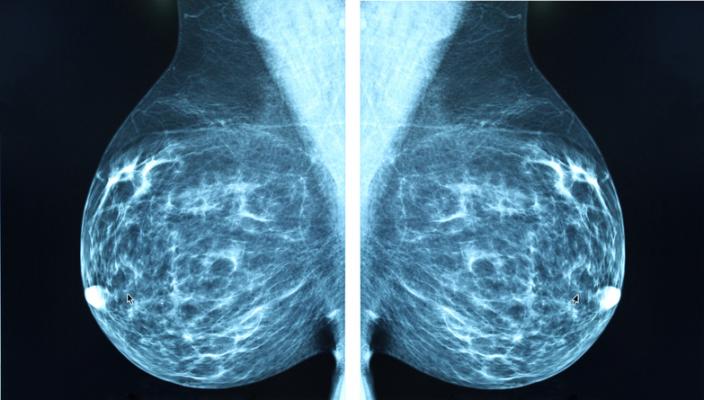

March 3, 2021 — Attendance at regular mammography screening substantially reduces the risk of dying from breast cancer, according to a large study of over half a million women, published in the journal Radiology. Researchers said women who skip even one scheduled mammography screening before a breast cancer diagnosis face a significantly higher risk of dying from the cancer.

Breast cancer screening with mammography has helped reduce disease-related deaths by enabling detection of cancer at earlier, more treatable stages. Despite mammography's well-established effectiveness, many women don't participate in recommended screening examinations.